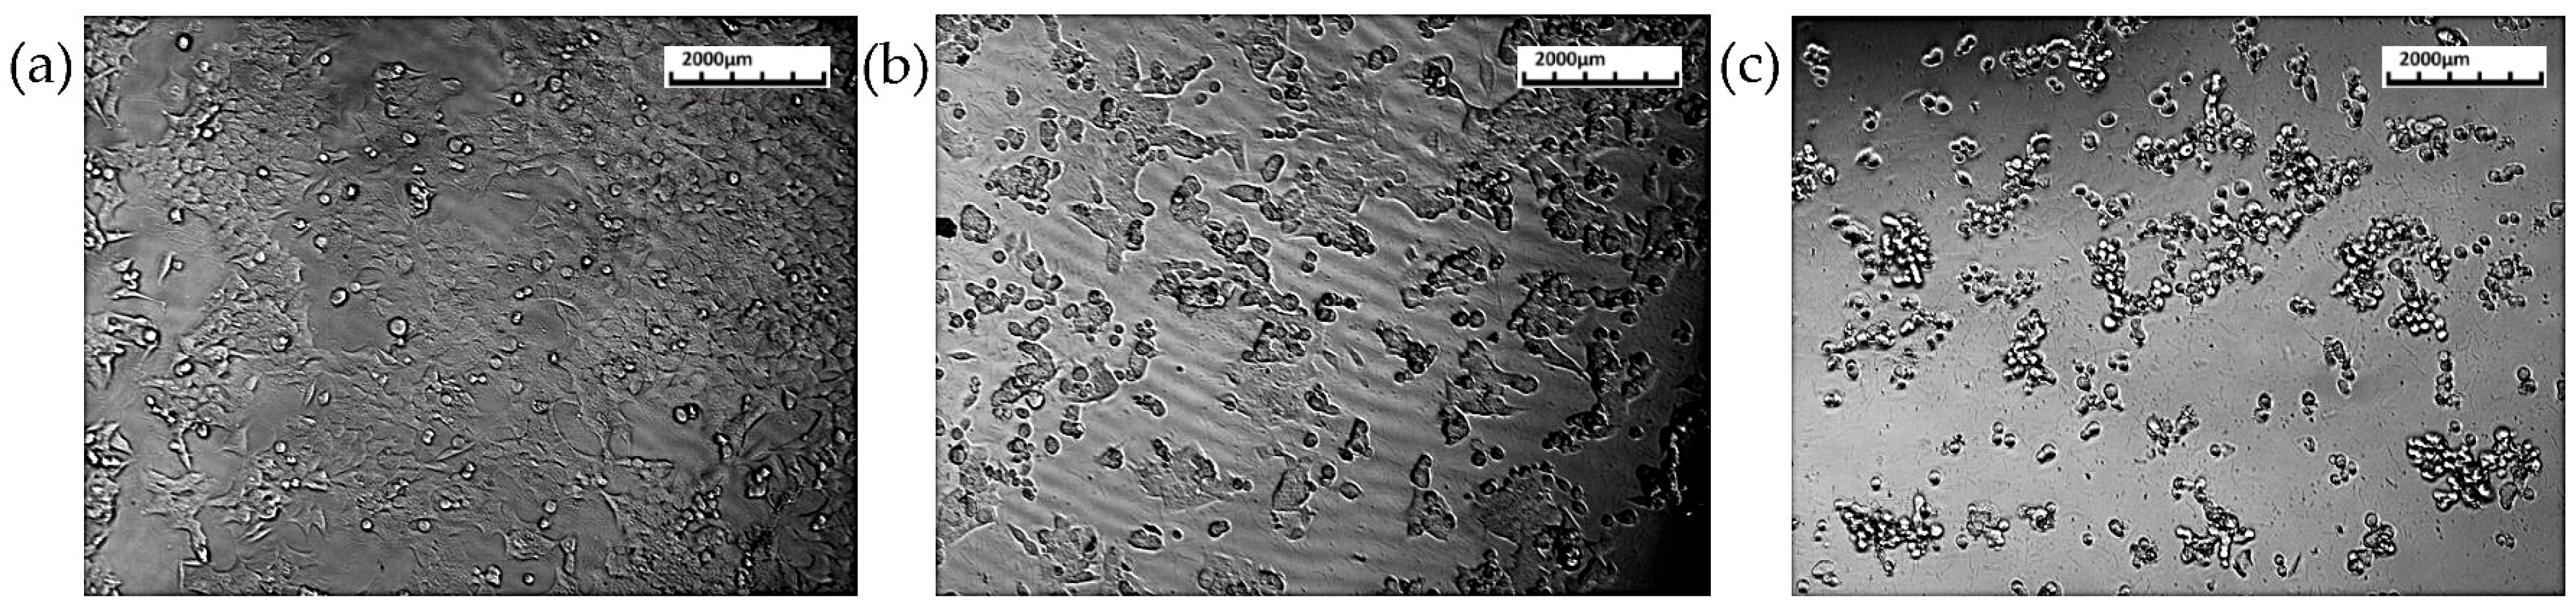

3.3. Cell Migration Assay

3.3.1. HCT116 Cell Lines

3.3.2. L929 Cell Lines